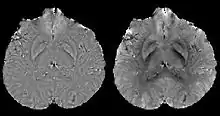

Thresholded K-space division (TKD)

The underdetermined data in Fourier domain is only at the location of the cone and its immediate vicinity. For this region in k-space, spatial-frequencies of the dipole kernel are set to a predetermined non-zero value for the division. Investigation of more advanced strategies for recovering data in this k-space region is also a topic of ongoing research.[16]

Thresholded k-space division[12][17] only requires a single angle acquisition, and benefits from the ease of implementation as well as the fast calculation speed. However, streaking artifacts are frequently present in the QSM and the susceptibility value is underestimated compared to COSMOS calculated QSM.